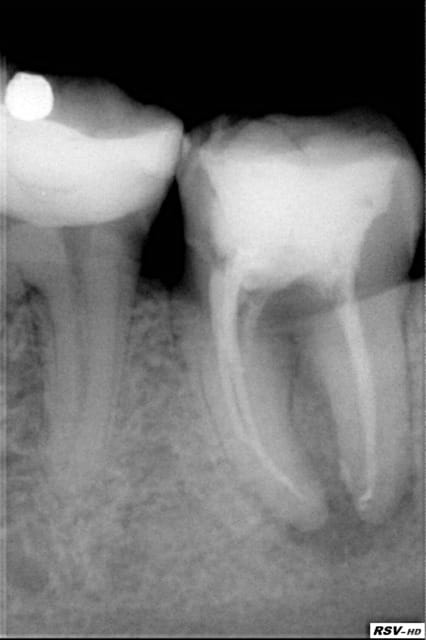

patiente vue en urgence decembre 2009, obturation + reconstitution + prov,revue une semaine après,plus de douleurs,fistule en voie de disparition

en fevrier RAS bien que l'image n'ait pas disparu(en 2 mois c'est impossible)

pose de la ceramique fin fevrier

RAS depuis

attendre oui mais pas non plus trop longtemps(risque de desct prov ou si tu n'en as pas fait,réinfiltration ou fracture,etc... )